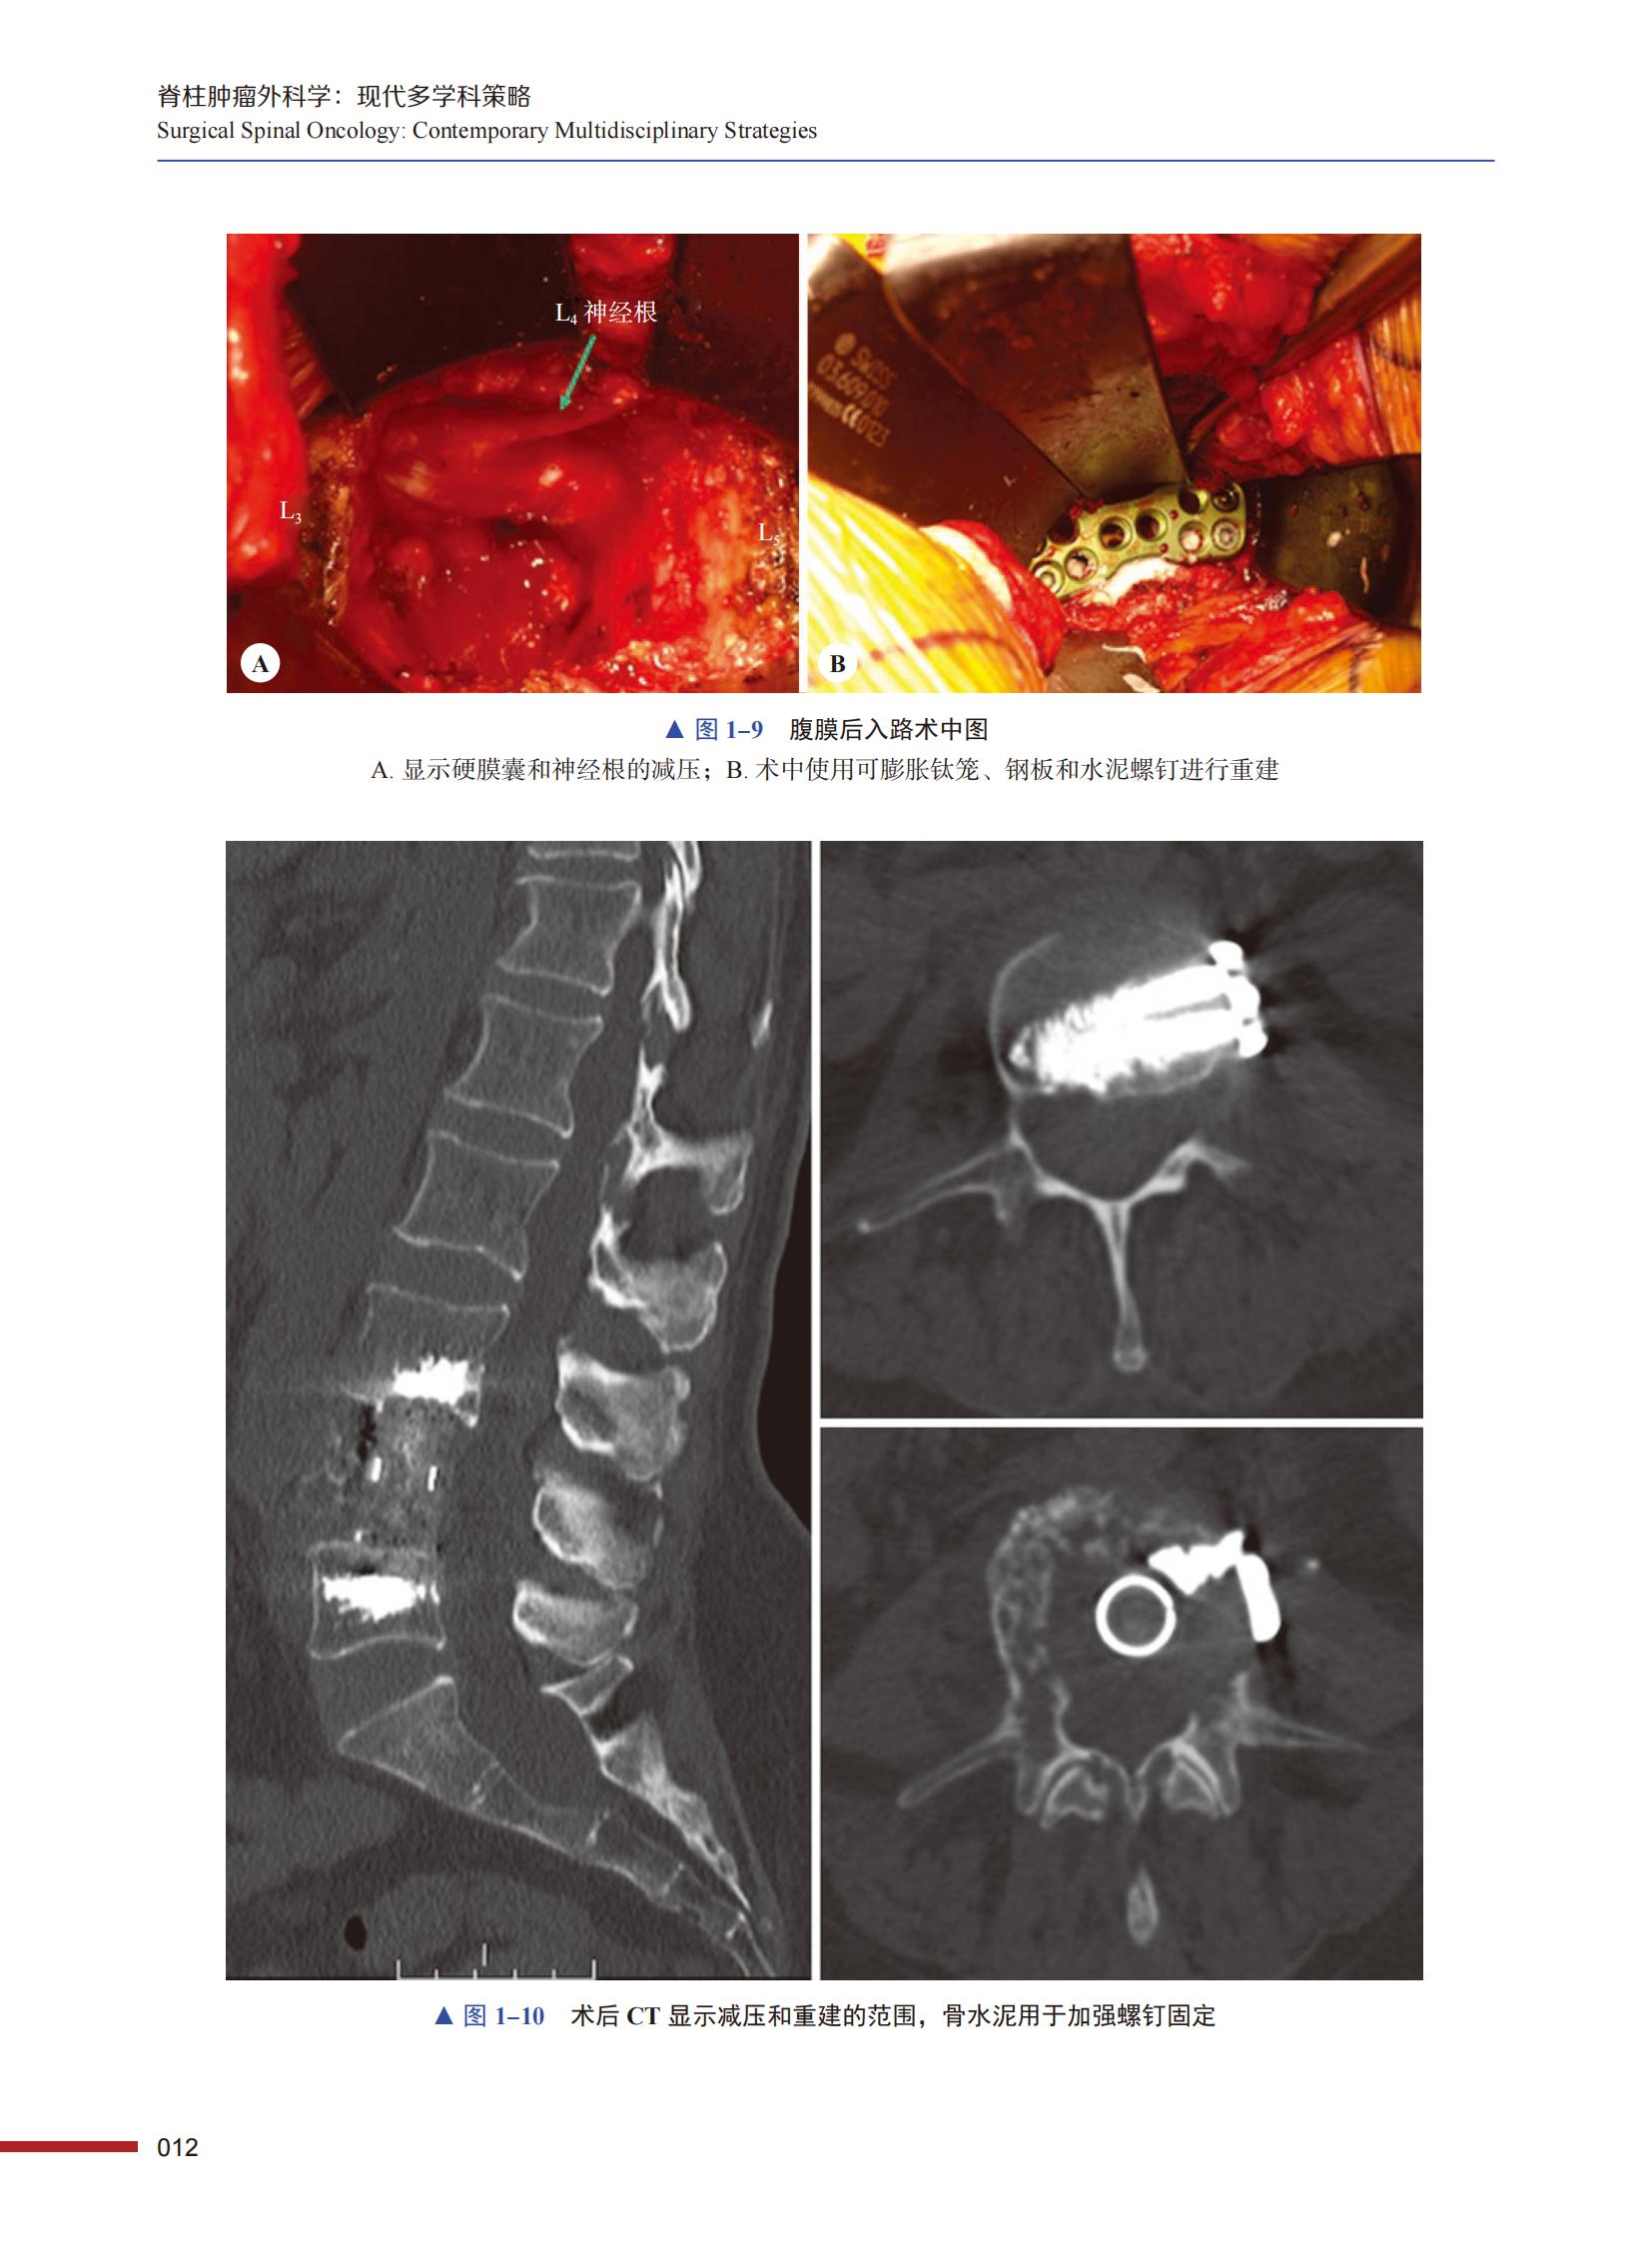

本书引进自 Springer 出版社,是一部系统介绍脊柱肿瘤外科学的实用著作。全书共四篇 22 章,不仅详细介绍了脊柱肿瘤的解剖、现代病理学、分类分期、影像学诊断等基础知识,还介绍了脊柱原发性肿瘤、脊柱转移瘤及特殊解剖部位肿瘤的现代治疗理念、治疗技术和现代微创治疗技术。书中所述内容均基于真实病例和术者经验,同时配有大量影像学和手术前后高清照片,为临床医师提供了丰富的参考资料,对国内从事脊柱外科临床工作的医师大有裨益。本书内容实用、图片丰富、言简意赅、重点突出,既可作为住院医师和入门脊柱外科医师的指导书,又可作为中、高级脊柱外科医师了解新技术、新理念的参考书。